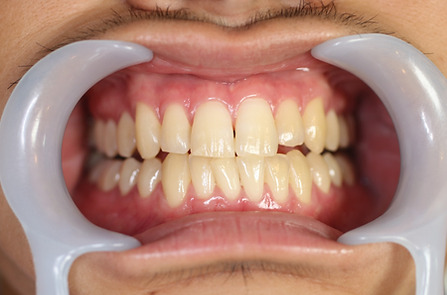

2ホワイトニング【治療例3】

治療前

治療後